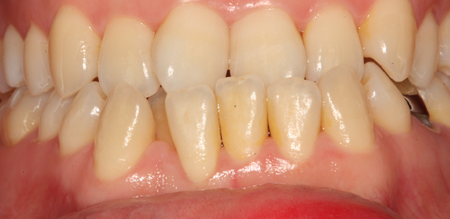

치주치료 전후사진

B

A

치주치료

청담네오플란트는 치주치료를 통하여 치아를 살릴 수 있는 기회를 놓치지 않습니다.

치주염(잇몸병)은 치아에 붙어있는 치석 및 세균 등에 의한 염증반응으로 잇몸뼈가 상실되는 질환을 말합니다.

초기에는 잇몸이 붓거나 잇몸에서 피가 나는 증상이 나타나며 계속 방치하면 치아를 발치해야 할 수도 있습니다.

치주치료는 이러한 치석 및 세균 등을 제거하여 잇몸뼈를 안정된 상태로 유지하는 시술을 말하며, 청담네오플란트에서는 치의학박사 / 전문의가 직접 시술하고 있습니다.

치주염 단계별 증상

건강한 상태

치아 주위의 잇몸이 핑크색을 띄며, 잇몸에서 피가 나지 않음.

스케일링을 6개월 ~ 1년 주기로 받고 올바른 칫솔질로 건강한 치주 조직을 유지

치은염 (초기~중기)

치아 주위의 잇몸이 붉게 부어 있으며, 칫솔질 등을 할 때 피가 남.

스케일링 주기의 조절이 필요할 수 있으며, 올바른 칫솔질을 시행하여야 함.

치주염 (중기~말기)

주기적으로 잇몸이 붓고 피가 나며, 욱씬하거나 우리한 통증이 나타남.

치주치료 및 정도에 따라 치주수술(잇몸수술)이 필요함. 향후 관리 정도에 따라 3~6개월 간격으로 내원하여 유지치료를 시행하여야 함.

치주염 (말기)

잇몸이 항상 부어 있으며, 이가

흔들리는 정도가 점점 심해짐.

치주치료가 필요하며, 정도에 따라 치아를 발치하여야 할 수 있음.